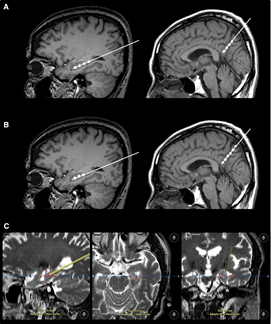

圖1 干細胞注射途徑

不僅如此,干細胞輸注治療安全可行。一項“立體定向腦內注射人間充質(zhì)干細胞治療AD病人”的臨床試驗結果表明,在治療結束后的24個(gè)月隨訪(fǎng)時(shí)間內,患者沒(méi)有出現與干細胞治療相關(guān)的嚴重的不良反應。

圖2 立體定向注射